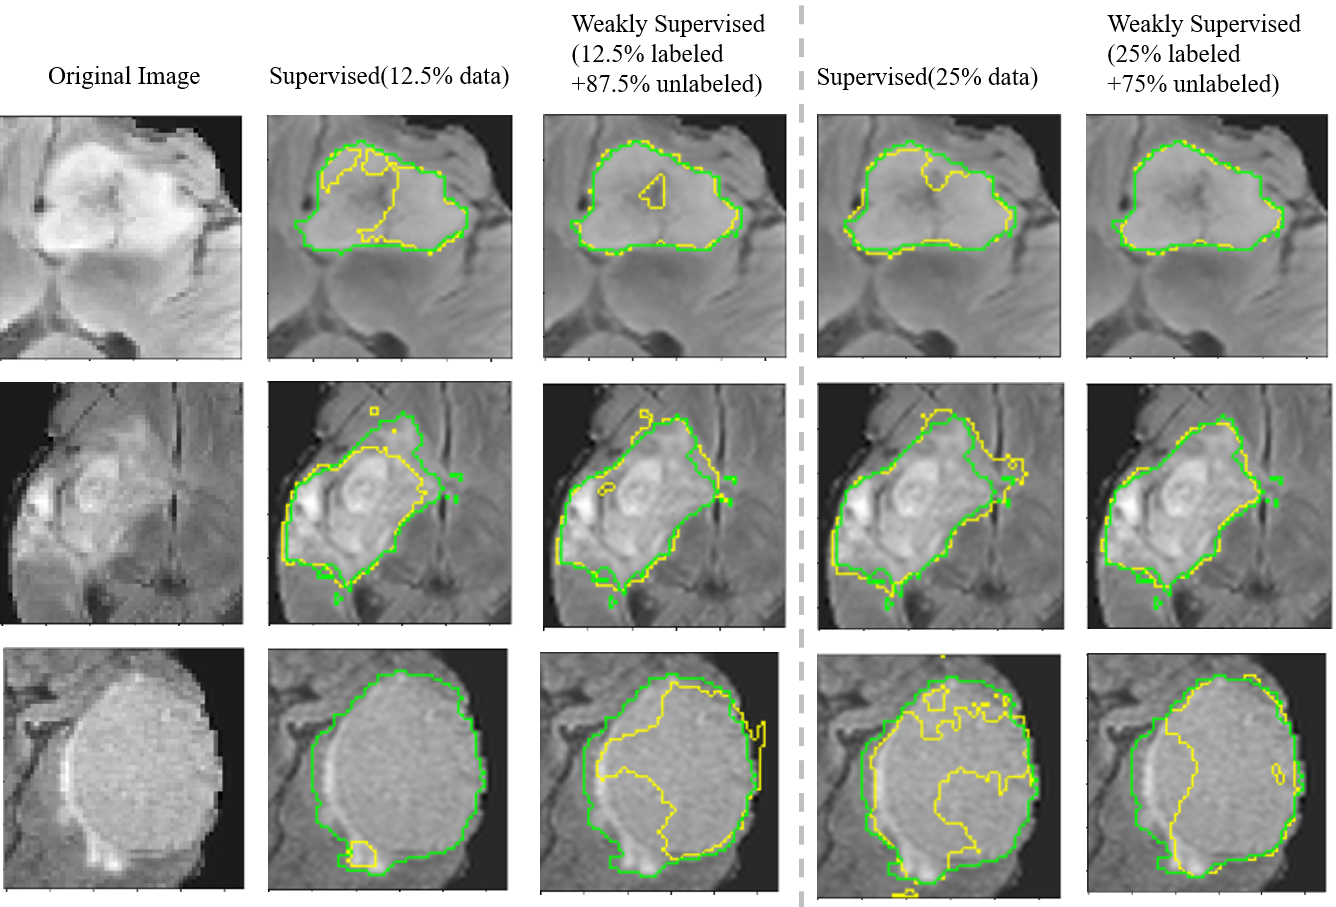

Refer to caption

Figure 7: Visualization of segmentation results by different methods. The green lines represent the boundaries of ground truth, and the yellow lines represent the predictive boundaries.

We compare MECCA with five state-of-the-art interactive segmentation methods: DeepIGeos Wang et al. (2018b)https://github.com/taigw/GeodisTK., InterCNN Bredell et al. (2018)https://github.com/gbredell/interCNN., IteR-MRL Liao et al. (2020) and BS-IRIS Ma et al. (2020). InterCNN is the multi-step version of DeepIGeos. We also introduce the SOTA method, U-Net Ronneberger et al. (2015)******https://github.com/liyun-lu/unet_and_vnet., of medical image segmentation as a comparable baseline. Table 2 show the quantitative comparison of the six interactive segmentation methods on different datasets. For a fair comparison, all CNN-based methods adopt the same network structure (P-Net), which is proposed in Wang et al. (2018b). We can see that our proposed MECCA performs better than other state-of-the-art methods on all three datasets. This study also visualizes the results in Figure 7, which shows that our method is more accurate in edge segmentation.

Figure 14: Qualitative segmentation results of MECCA for BraTS2015 validation set. The first column shows the cropped original images. The second to fifth columns respectively show: the result of supervised learning only using 12.512.512.5% of labeled data, the results of weakly-supervised learning using 12.512.512.5% labeled and other unlabelled images, the result of supervised learning only using 252525% of labeled data, the results of weakly-supervised learning using 252525% labeled and other unlabelled images. Both supervised learning and weakly supervised learning is based on our proposed method.